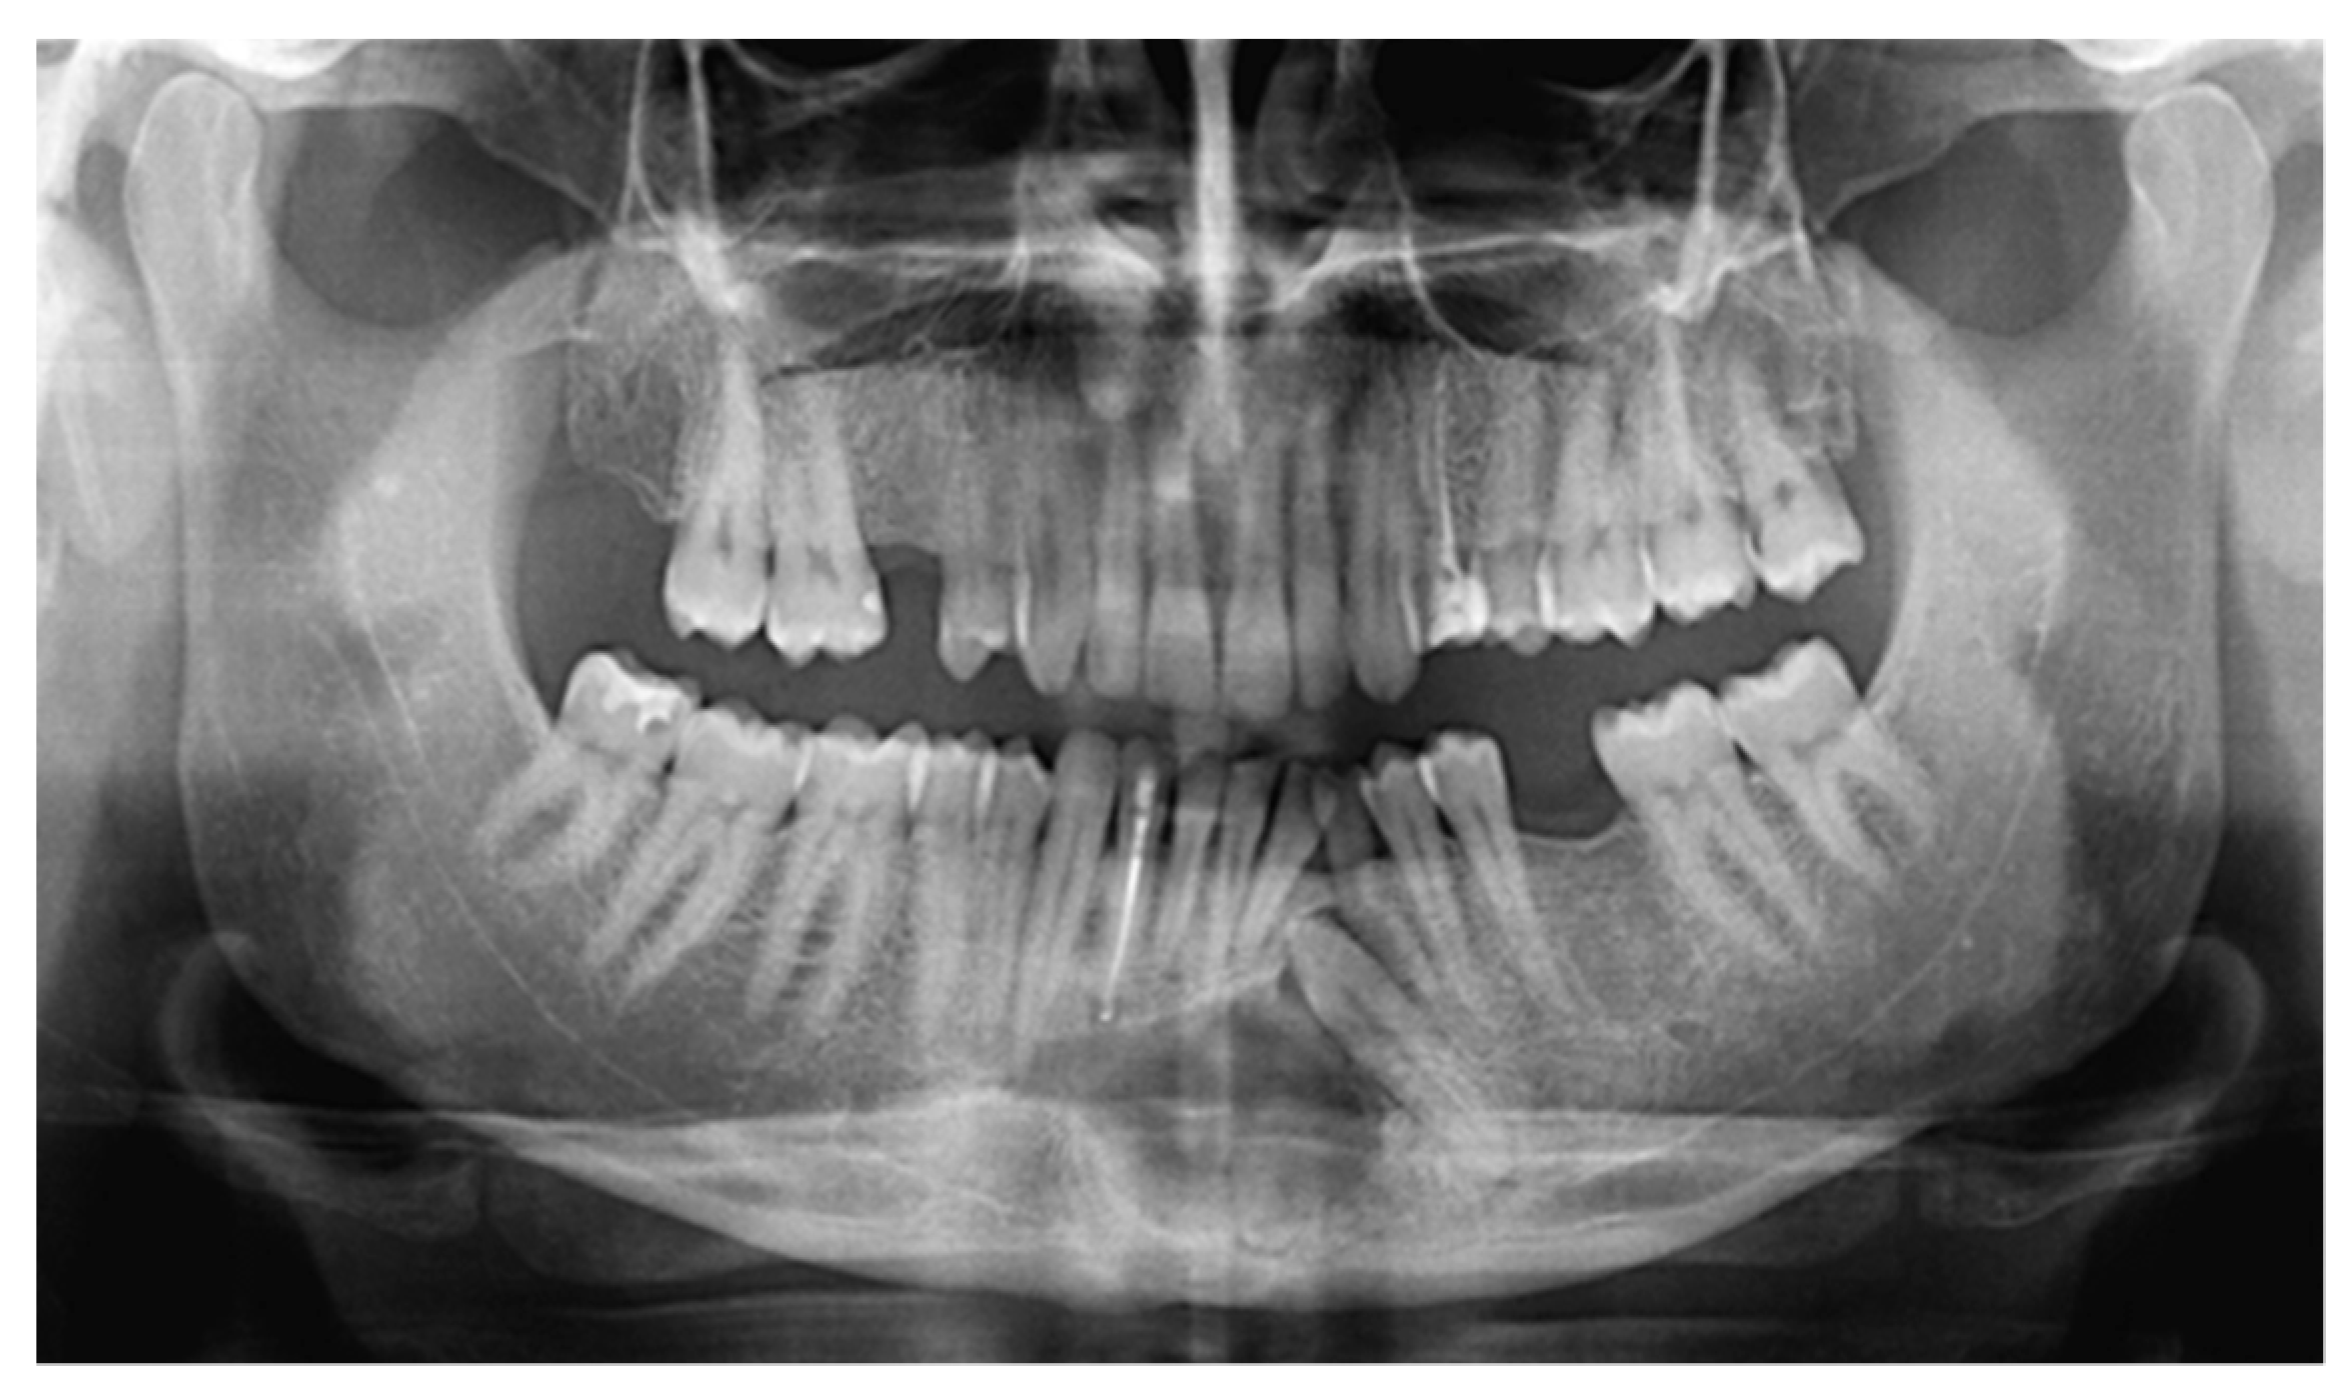

For oncological staging, the patient had orthopantomography, preoperative CT and MRI (Figure 6) of the head and neck, CT of the thorax, all with and without contrast, ultrasound echography of the neck and abdomen, a rhino-pharyngo-laryngeal fibroscopy and an angio-CT of the inferior limbs. No secondary lesions nor lymph node invasion were detected in preoperative staging.

Figure 6.

Preoperative MRI, multiple axial views. Vestibular extraosseous spread of the tumor was evident.

In our case, orthopantomography (Figure 1) and CT (Figure 2) showed a uniloculated 38 × 14 mm osteolytic area affecting the chin symphysis and extending in the left paramedian region. The lesion interrupted the vestibular bone cortex but spared the lingual one.

MRI with gadolinium-contrast represents a second-level examination essential for tumor staging, and in our case, the extent of the lesion through the anterior cortex erosion in the soft tissues of the chin was documented (Figure 6).